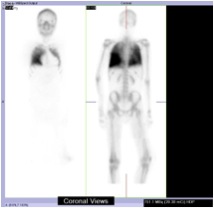

As a result of that, the patient might need to go through a long list of investigations. After assessing this patient and reviewed the CT images; we found that there was significant discordant between the alarming CT features and the totally asymptomatic clinical status. This discordance made metastatic calcification the most likely diagnosis. Bone scan was then arranged(picture 4) which showed intense uptakes in patient’s both lungs that almost equal to the uptake of bone.

For our patient, we did not resume the empirical TB treatment. His PET scan (picture 5) demonstrated active uptake in BHL and also the classical Panda sign compatible with sarcoidosis